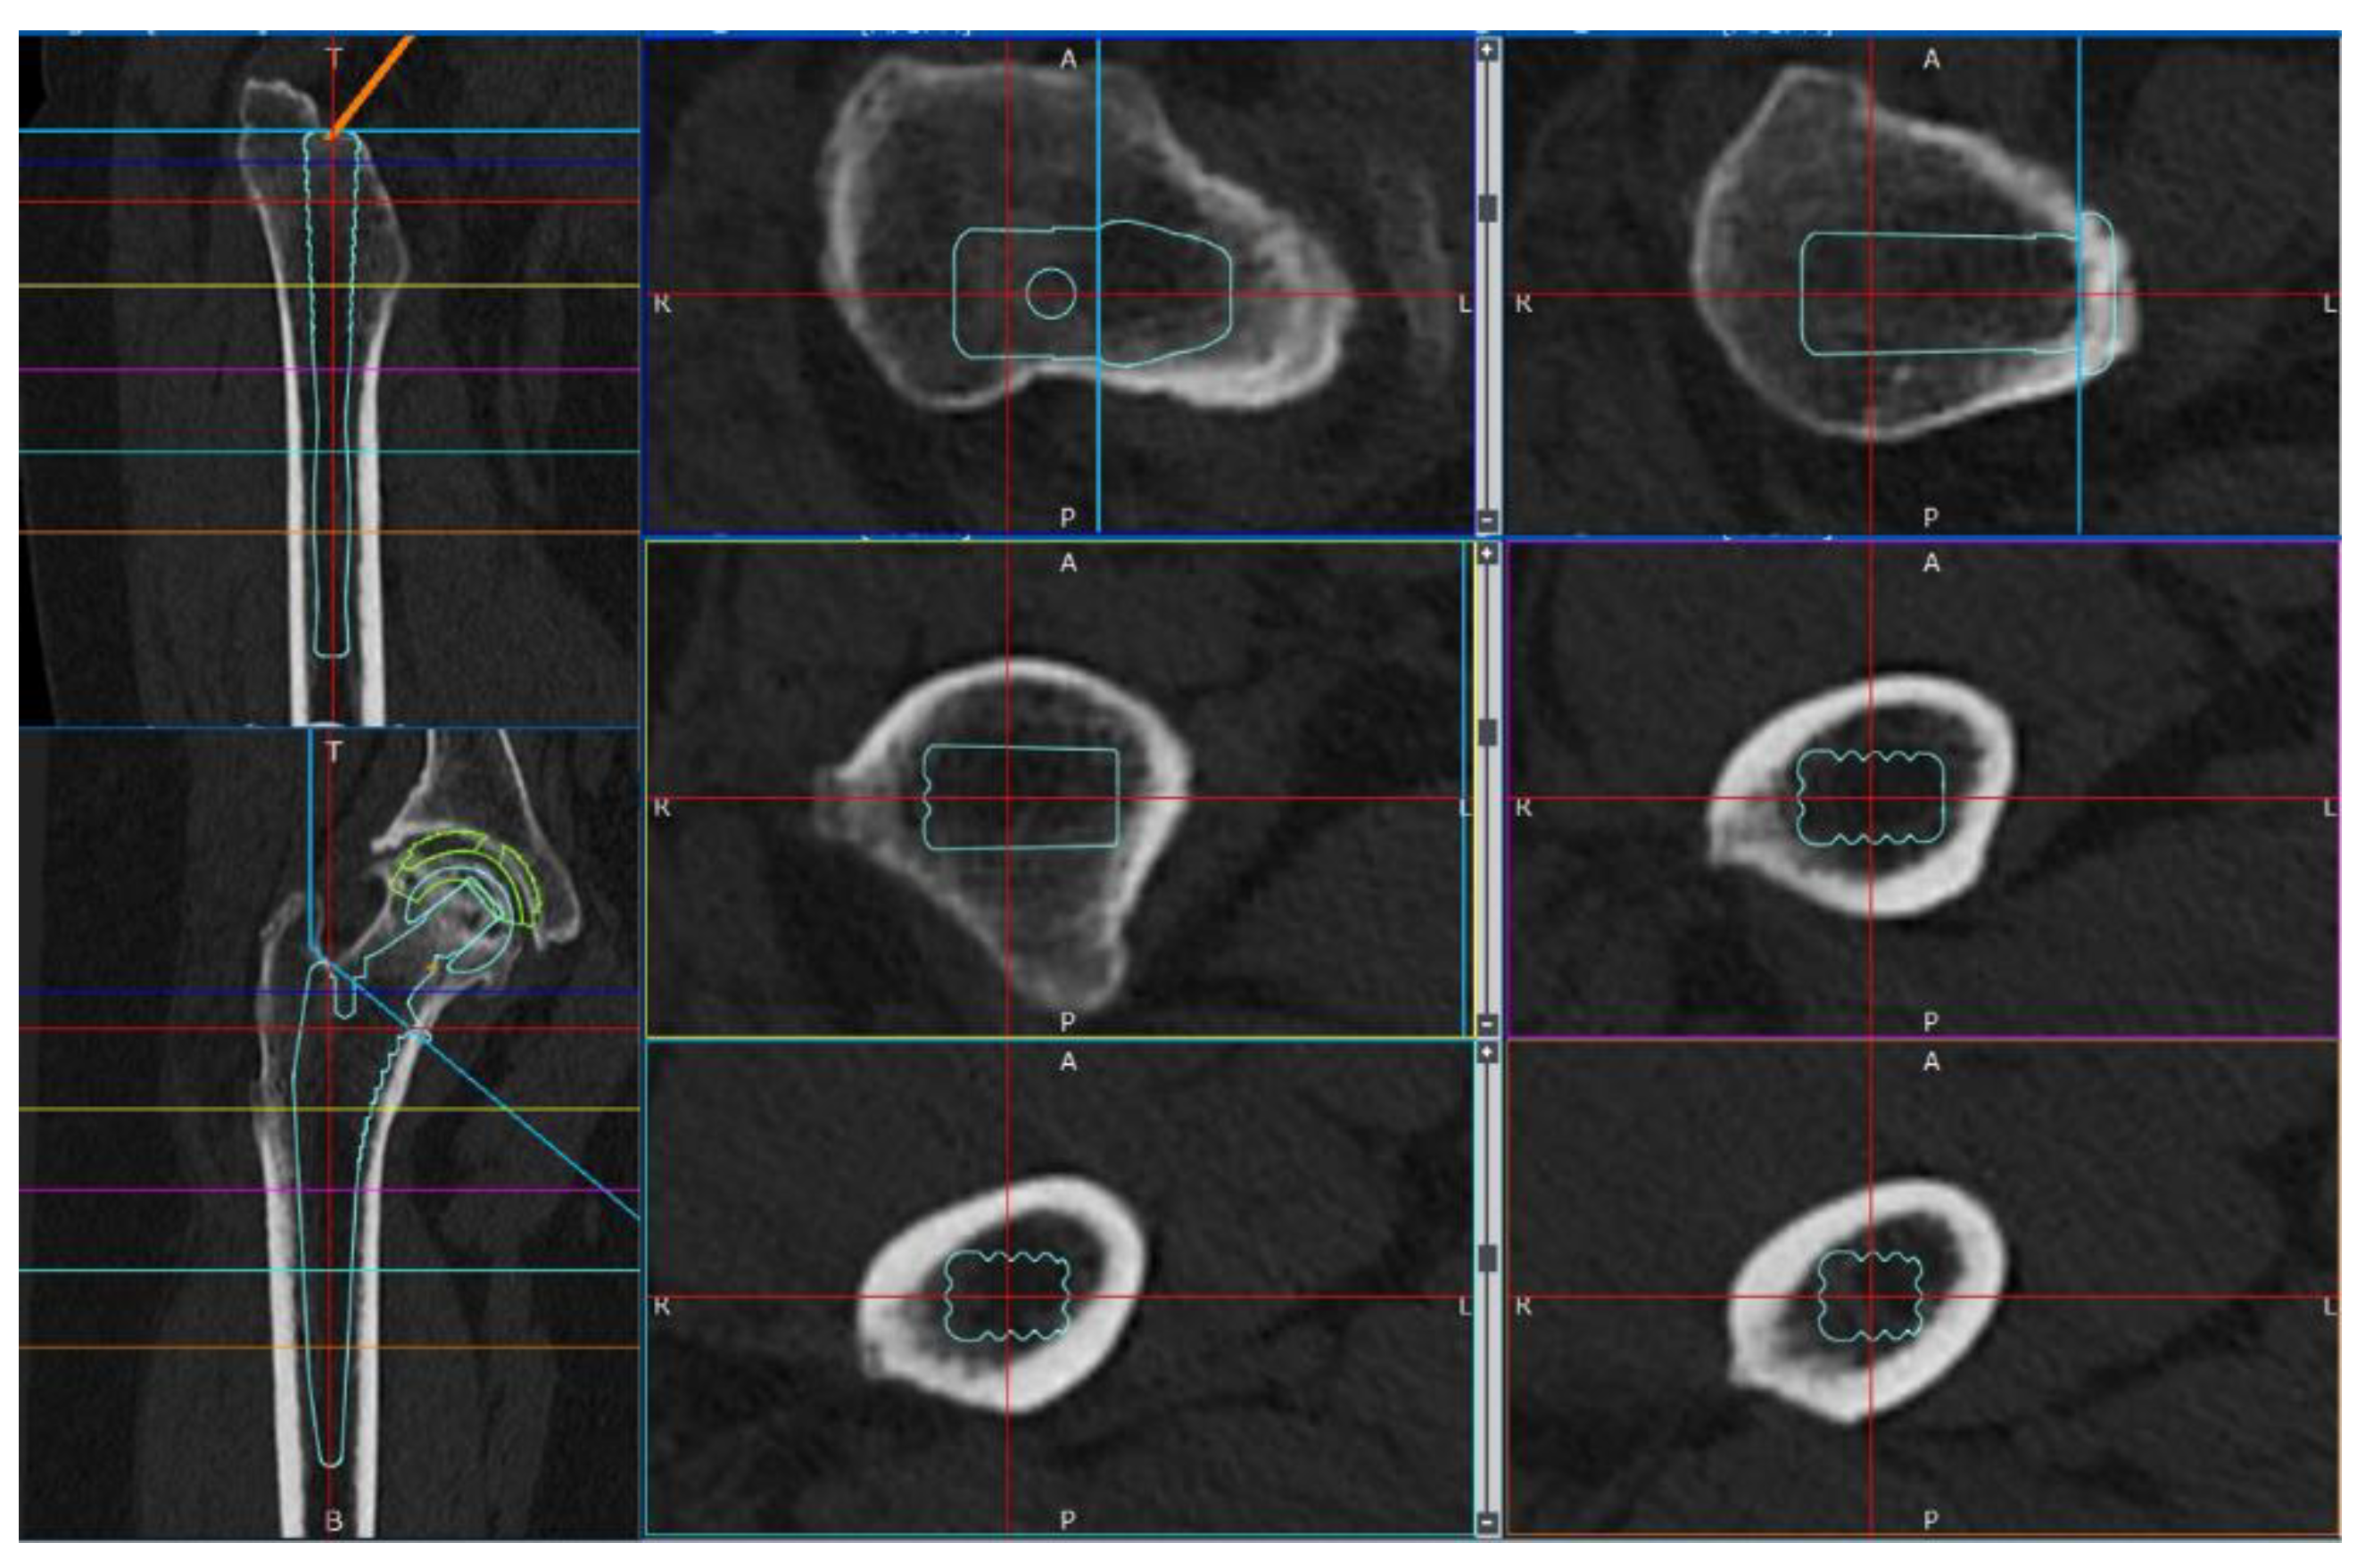

Simulations were conducted under a load to analyze the femoral stress distribution for each stem length. The femoral neck osteotomy and stem placement positions were initially planned using the 3D preoperative planning software, ZedHip (version 17.0.0; Lexi Co., Ltd., Tokyo, Japan) (Figure 2), and were faithfully reproduced in the MF.

Figure 2. Preparation for cTHA using ZedHip. Preoperative planning was performed using the 3D ZedHip software.